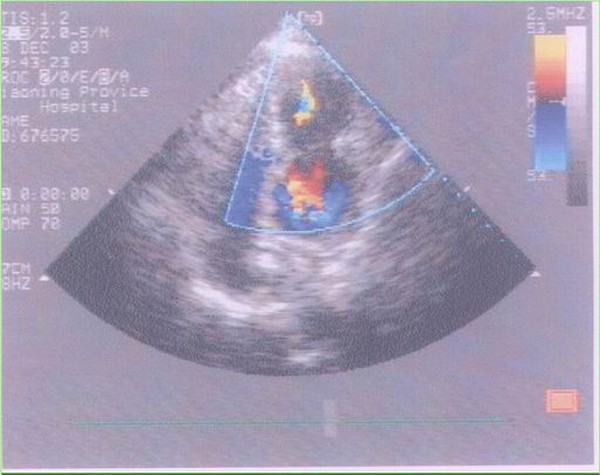

体表超声心动图:?下壁心肌梗死(下壁心肌运动减弱)。

临床所见:异常肥厚肌束或纤维肌隔将左心室分成主副两个腔。主腔通常位于基底部,与二尖瓣口和主动脉瓣口相连,副腔位于心尖部或主腔左外侧,与主腔通过一小孔或小梁间隙相通。

诊断方法:超声心动图和/或冠状动脉造